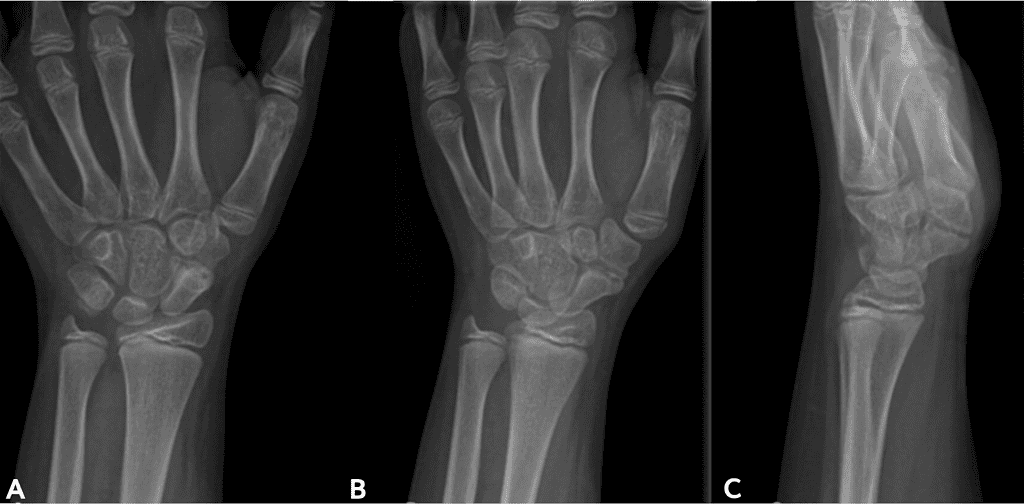

Figures 1-3 below descript the patient initial medical condition and subsequent surgical procedures prior to use of OSSIOfiber® implants

Screenshot 2026 01 20 At 2.48.03 Pm Ossio – Naturally Transformative Bone Healing

Figure 2: Post-operative X-rays taken January 2023,following first surgery, using metal K-wires.

Oblique thumb view [A] and Lateral thumb view [B]